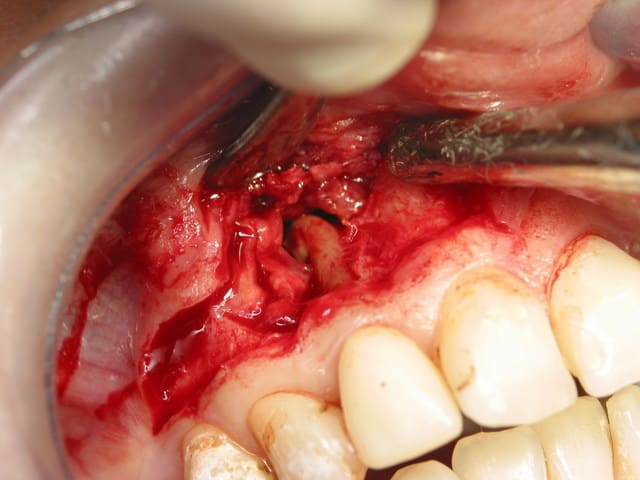

beau petit dépassement, j étais sur la plancher du nez, le kyste fleurtait avec ma membrane de schroeder au niveau de la canine. Pas de CBS. Chir a retro sur la latérale.

Alors ensuite ca se discute, j ai mis du bioos + tratracycline + membrane. Les endo n'aiment pas le bioos et preferent laisser le perioste jouer le role de membrane naturelle. Manque de bol ici, la partie vestibulaire de la corticale a explosee en petits éclats tres fins et une grosse fibrose a épaissie la muqueuse gingivale. j'ai du tous dissequer pour que ca soit propre.

photo 2 en distal de la racine de 12 on voit l'enveloppe du kyste qui est crevé alors qu en mesial on voit encore la corticale sur 11. au dessus de la racine de la 12, tu peux voir le tissus fibreux et des petits éclats osseux qui sont les restes de la corticale externe. Ce kyste s'invagine jusqu'au plancher nasal et a mangé un peu la paroi du sinus en mésail de 13 rentrant en communication avec la membrane de schroeder. Lors du decollage de la membrane kystique, ces deux facias se sont parfaitement decollées l un de l autre (ouf). De l autre coté, j'ai decollé le kyste de lors du palais. Bref une belle cavité de plusieurs centimetres cubes.